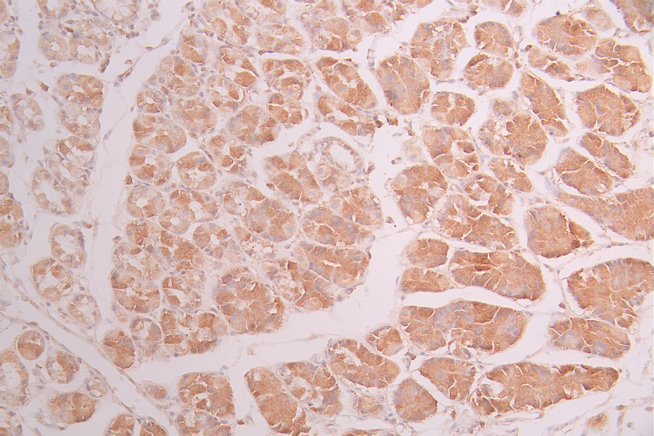

IHC image of CSB-RA597007A0HU diluted at 1:100 and staining in paraffin-embedded human breast cancer performed on a Leica BondTM system. After dewaxing and hydration, antigen retrieval was mediated by high pressure in a citrate buffer (pH 6.0). Section was blocked with 10% normal goat serum 30min at RT. Then primary antibody (1% BSA) was incubated at 4°C overnight. The primary is detected by a Goat anti-rabbit polymer IgG labeled by HRP and visualized using 0.05% DAB.

IHC image of CSB-RA597007A0HU diluted at 1:100 and staining in paraffin-embedded human stomach tissue performed on a Leica BondTM system. After dewaxing and hydration, antigen retrieval was mediated by high pressure in a citrate buffer (pH 6.0). Section was blocked with 10% normal goat serum 30min at RT. Then primary antibody (1% BSA) was incubated at 4°C overnight. The primary is detected by a Goat anti-rabbit polymer IgG labeled by HRP and visualized using 0.05% DAB.